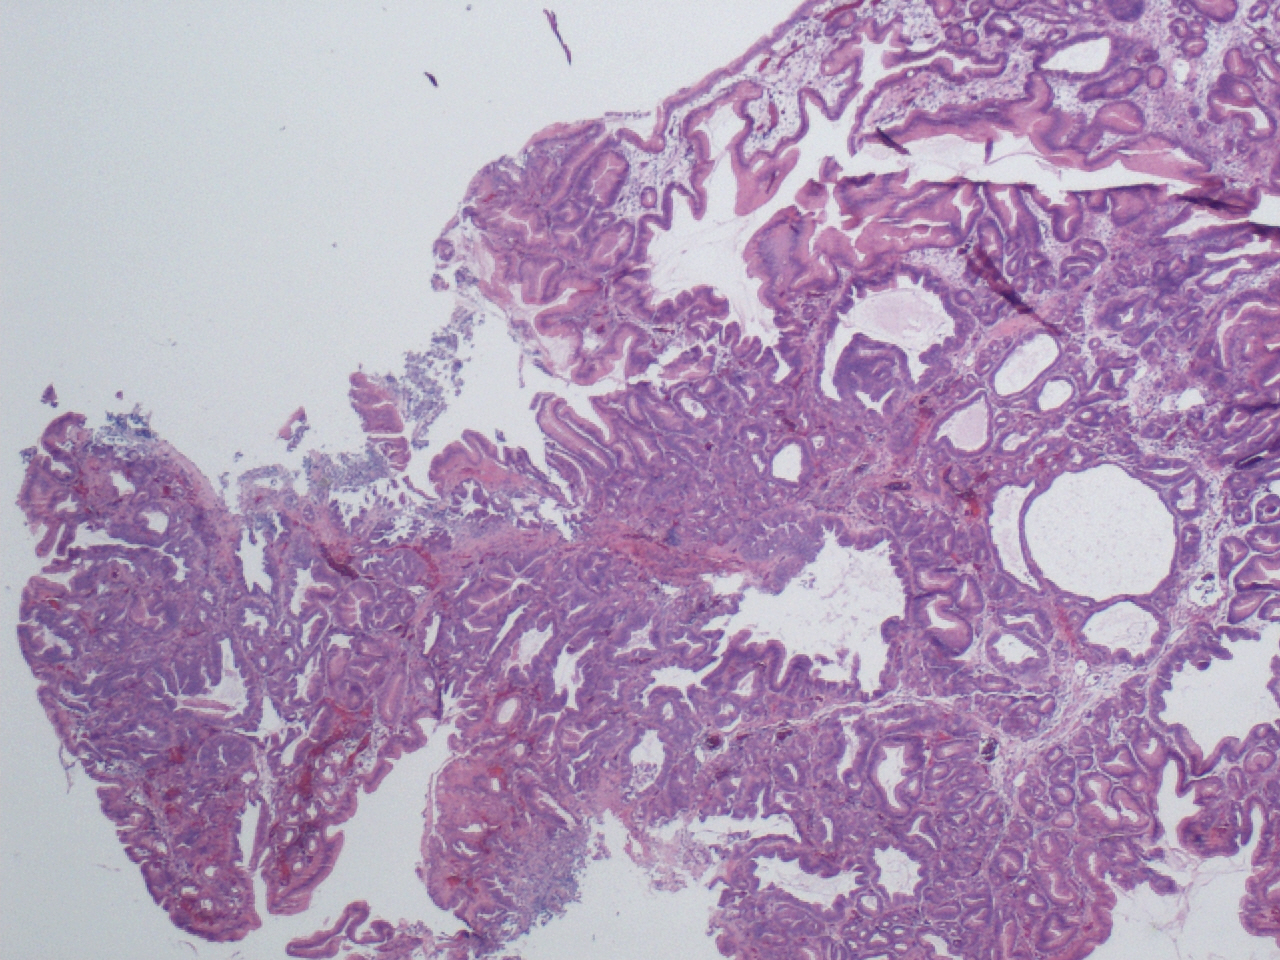

Карнификация Легкого: Микропрепараты и Диагностика

Раздел: Калейдоскоп образов